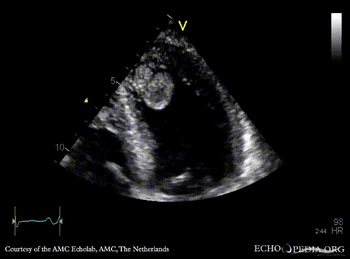

Case 142